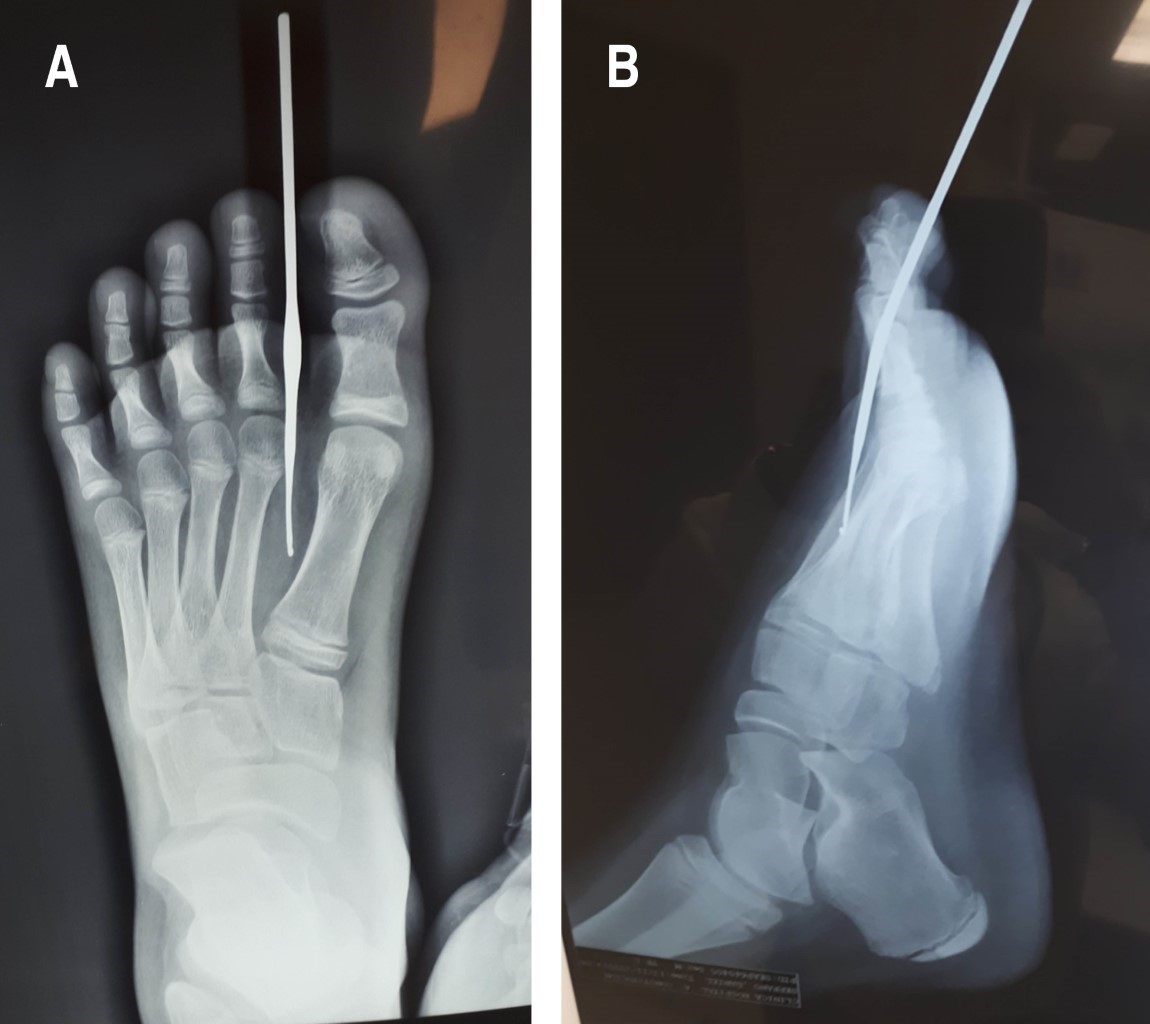

Se trata de un paciente masculino de 11 años, quien inició su padecimiento dos horas previo a su valoración en el servicio de urgencias. El paciente refirió que al encontrarse corriendo sin calzado en su hogar y, de manera inadvertida, pisó una aguja para tejer tipo crochet, por lo que se trasladó para su valoración. A su ingreso se encontró estable, con facies de dolor y con aguja para tejer tipo crochet incrustada en región interdigital del primer y segundo ortejos izquierdos (Figura 1), sin datos de sangrado activo.

En radiografías en dos posiciones de la extremidad afectada se observó el objeto extraño incrustado en tejidos blandos, pero sin afectación ósea (Figura 2).

Figura 1

Figura 2